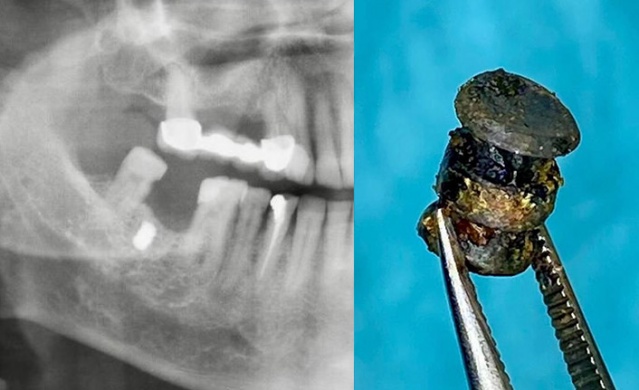

Yanağına saplanan metal parçasıyla 15 yıl yaşadı

Yanağına saplanan metal parçasıyla 15 yıl yaşadı. Foto Galeri